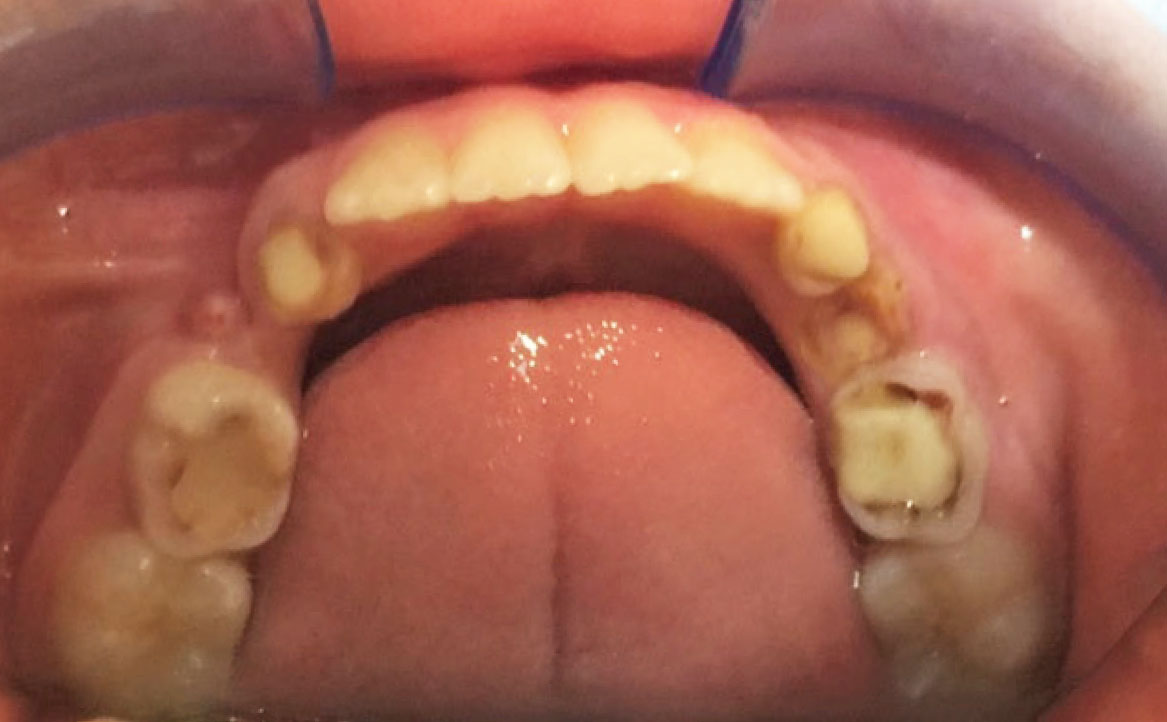

Dall’esame obiettivo intra orale si osservava una seconda classe canina destra e sinistra, una seconda classe molare destra e sinistra, e un diametro inter-canino e inter-molare ridotto sia in riferimento al mascellare superiore sia al mascellare inferiore (fig. 3A-3E).

Un paziente maschio di 8 anni si è presentato in prima visita presso il dipartimento di odontoiatria dell’IRCCS Ospedale San Raffaele di Milano. Dall’anamnesi e dalla valutazione clinica svolta con la collaborazione del reparto di pedodonzia, è stata evidenziata una condizione di dentizione mista, la presenza di alcuni elementi dentali con trattamenti odontoiatrici pregressi incongrui e una scarsa igiene orale.

Il paziente si è recato in prima visita presso il dipartimento di odontoiatria dell’IRCCS Ospedale San Raffaele di Milano. In seguito a una completa anamnesi medica e odontoiatrica, e dopo aver eseguito una valutazione ortodontica e pedodontica, è stato definito un iter terapeutico composto da più fasi. All’esame obiettivo questo mostrava alta cariorecettività con scarsa igiene orale, contrazione palatale e arcate superiore e inferiore contratte.